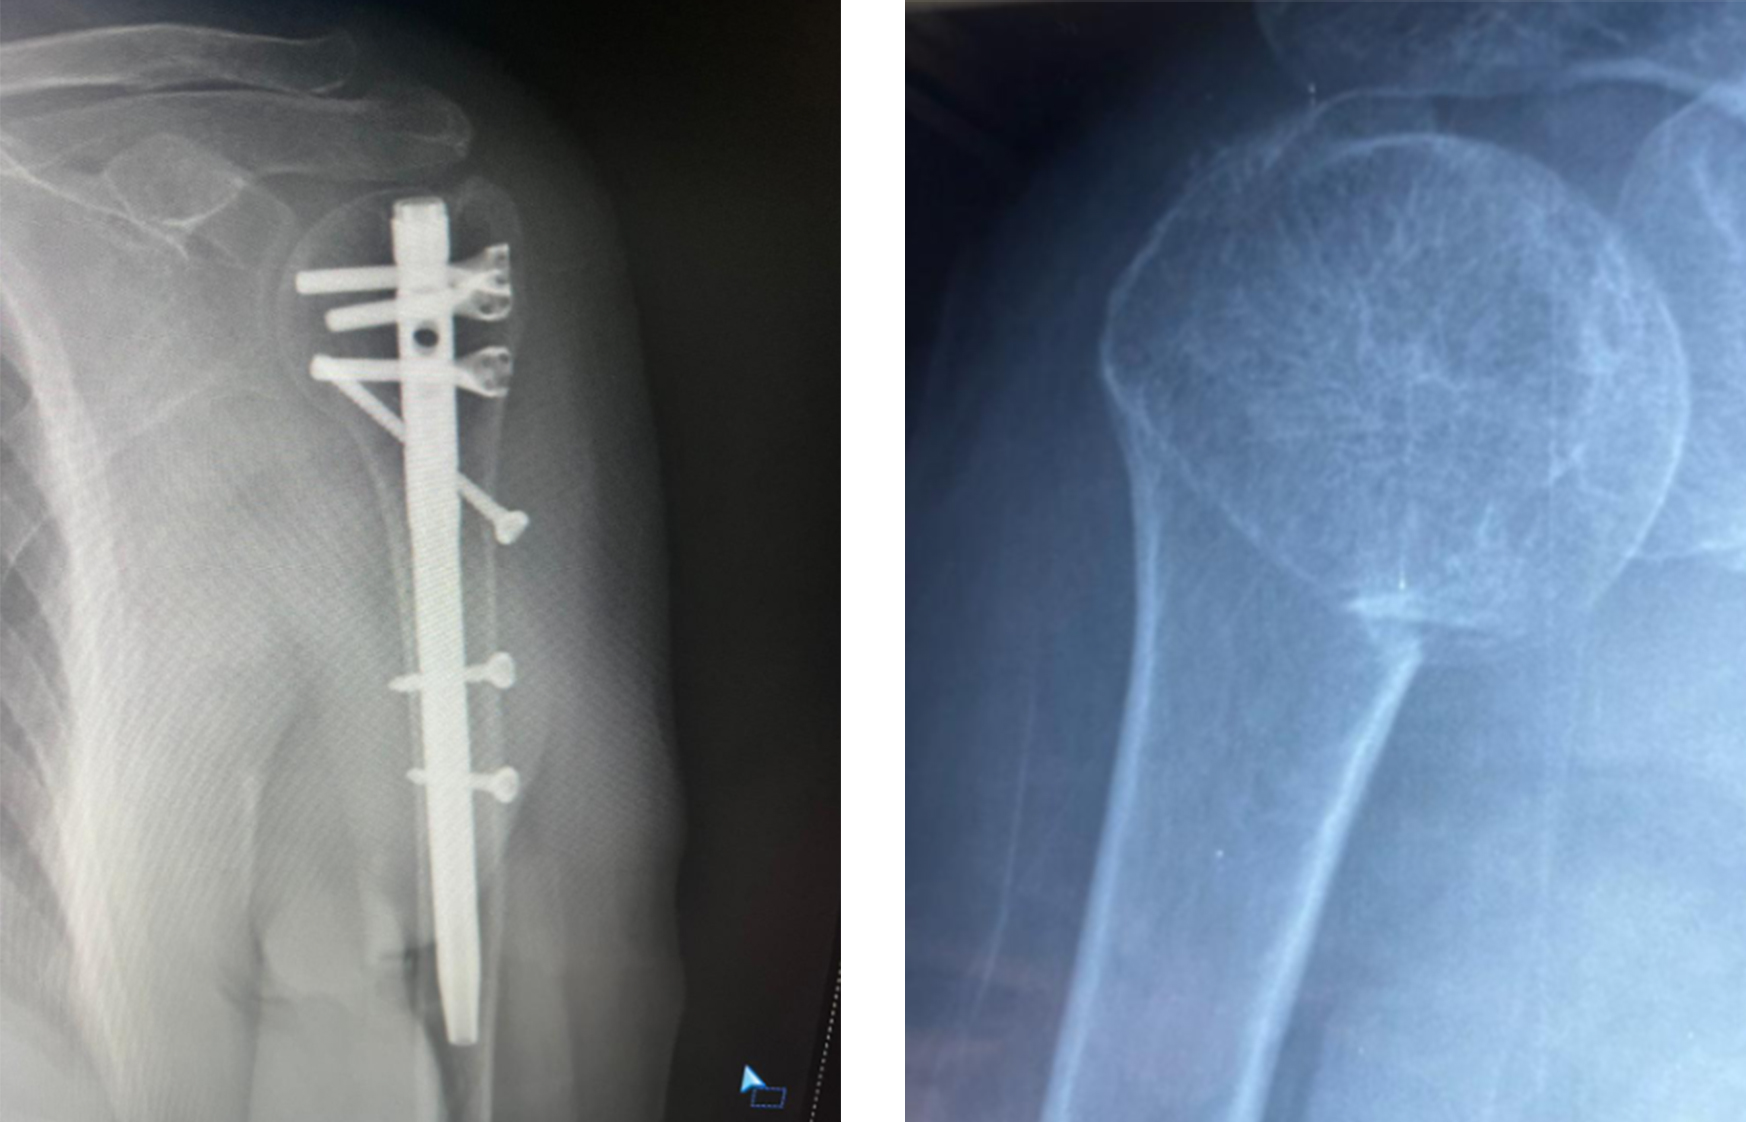

Fixation par plaque de verrouillage (ORIF)

La fixation par plaque verrouillable est largement utilisée pour les fractures proximales de l’humérus, en particulier dans les os ostéoporotiques. Il assure une stabilité angulaire et permet une mobilisation précoce.

Chirurgie orthopédique de fixation par plaque de verrouillage de l

application chirurgicale de fixation par plaque de verrouillage de l

Avantages des systèmes de plaques de verrouillage

• Fixation haute stabilité

• Convient aux os ostéoporotiques

• Conception de vis multi-angles

• Favorise une rééducation précoce